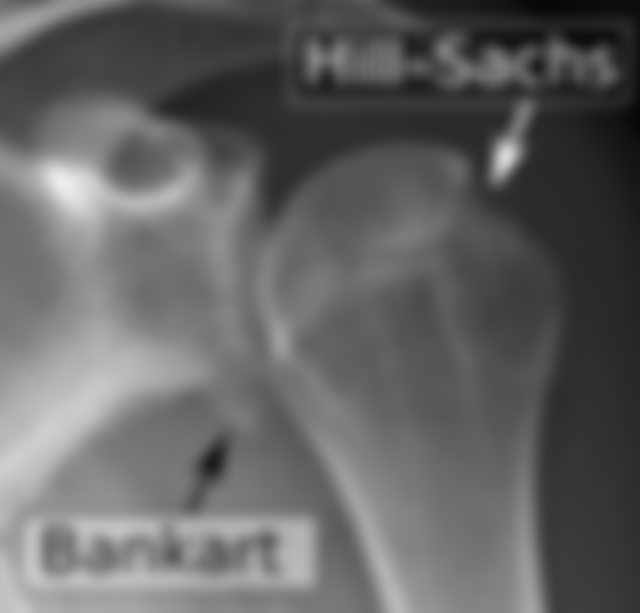

72.47 歲男性主訴受傷後右肩痛,右肩 X 光正位及內旋影像顯示如圖,下列敘述何者錯誤?

(A)無法評估有無旋轉肌斷裂(rotator cuff tear)

(B)没有 bony Bankart 症灶

(C)病人可能有肩關節不穩定的問題

(D)可以看到 Hill-Sachs 病灶